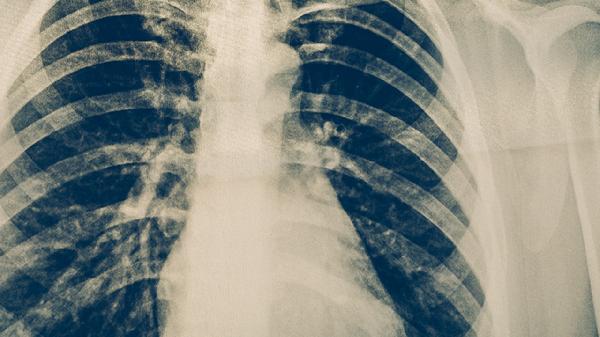

肺结核患者的营养原则

肺结核患者的营养原则主要包括高热量、高蛋白、高维生素、适量矿物质和充足水分摄入。合理的营养支持有助于改善患者免疫功能,促进病灶修复,减少药物不良反应。